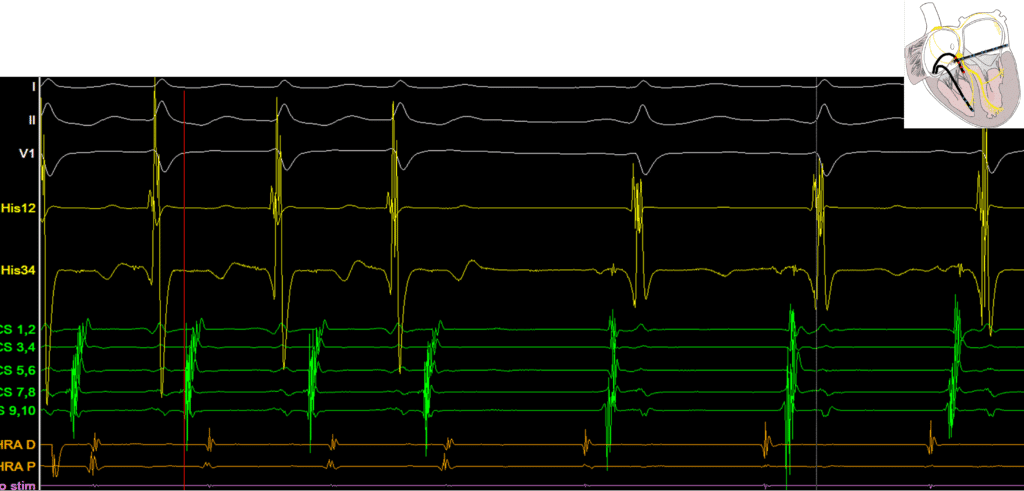

During an SVT study, an SVT was repeatedly non-sustained and spontaneously terminated resulting in the following EGMs. No manoeuvres could be successfully performed. Given the EGM, can any inferences be made about the likely SVT sub-type?

Answer: A (visually) long VA time makes slow/fast AVJRT unlikely. Spontaneous termination with the atrium as the last EGM of tachycardia makes Focal AT unlikely.

The Above EGM demonstrates a narrow complex tachycardia with a VA time of 110ms and eccentric atrial activation. This is strongly suspicious for ORT.

Termination occurs in the Ventricle in this scenario. What does this tell us?